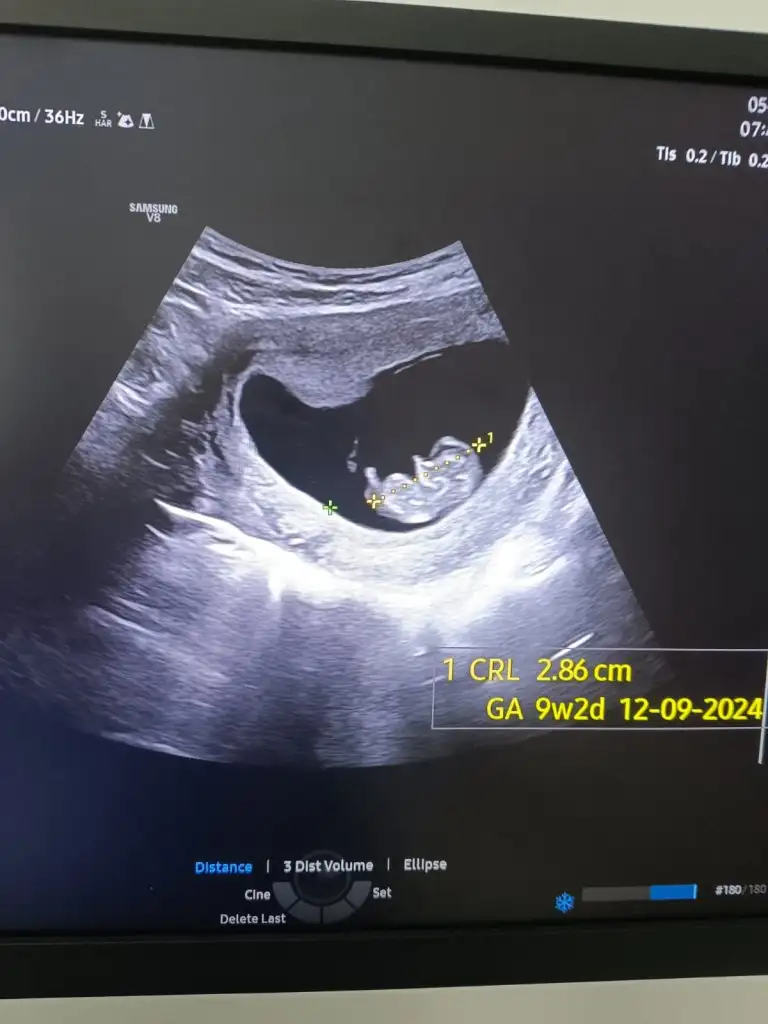

Merhaba 12+2 haftalık rica etsem banada cinsiyet tahmini yapabilir misiniz sırasıyla 5 hafta 7 hafta ve 12+2 haftalık

Kız gıbı cnm nup düz geldı bana hayırlısıyla saglıklı gelsın dünyaya kuzun